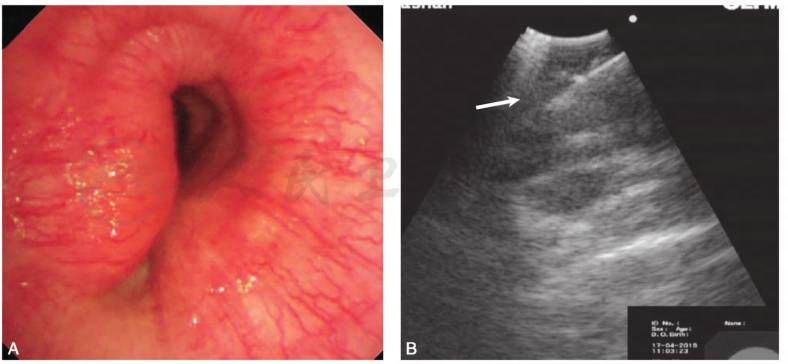

电子支气管镜及超声支气管镜检查(图4):气管中段外压性狭窄70%~80%,距声门约7cm,黏膜表面光滑,伴充血,未见出血。左右主支气管及各级支气管镜下未见明显异常。超声支气管镜于病变处可探及不规则低回声区。病变处行针吸活检,完善病原学涂片及培养,特殊染色及病理等检查。

图4 电子支气管镜及超声支气管镜检查

A.电子支气管镜示气管中段外压性狭窄70%~80%,距声门约7cm,黏膜表面光滑,伴充血;B.支气管镜超声于病变处可探及不规则低回声区(白箭)

引自:主编:.呼吸与危重症医学疑难与危重病例精选.第1版.ISBN:978-7-117-30147-3